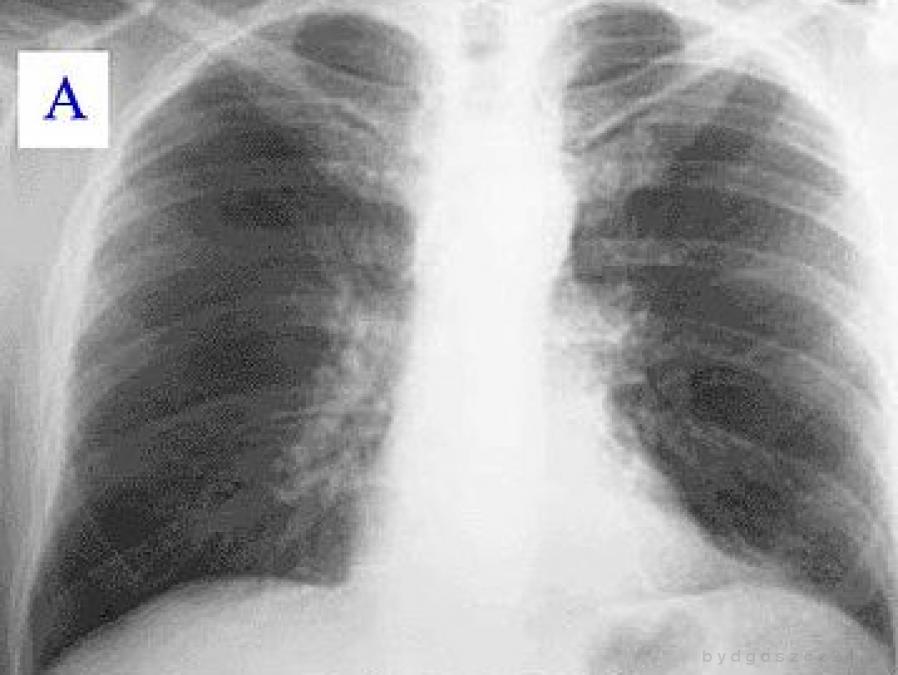

Spirometria pozwala wykazać nieprawidłowe funkcjonowanie płuc, np. obturację (zwężenie) dróg oddechowych, zanim jeszcze pojawią się poważniejsze dolegliwości. W przypadku stwierdzenia choroby, badanie umożliwia określenie stopnia jej zaawansowania oraz tempa progresji.